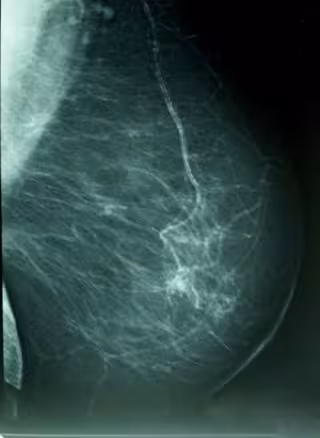

Científicos del CIEMAT desarrollan métodos precisos para predecir metástasis de cáncer de mama y de pulmón

Cáncer De Mama, Densidad Mamográfica

WIKIPEDIA/A. AVENDAÑO